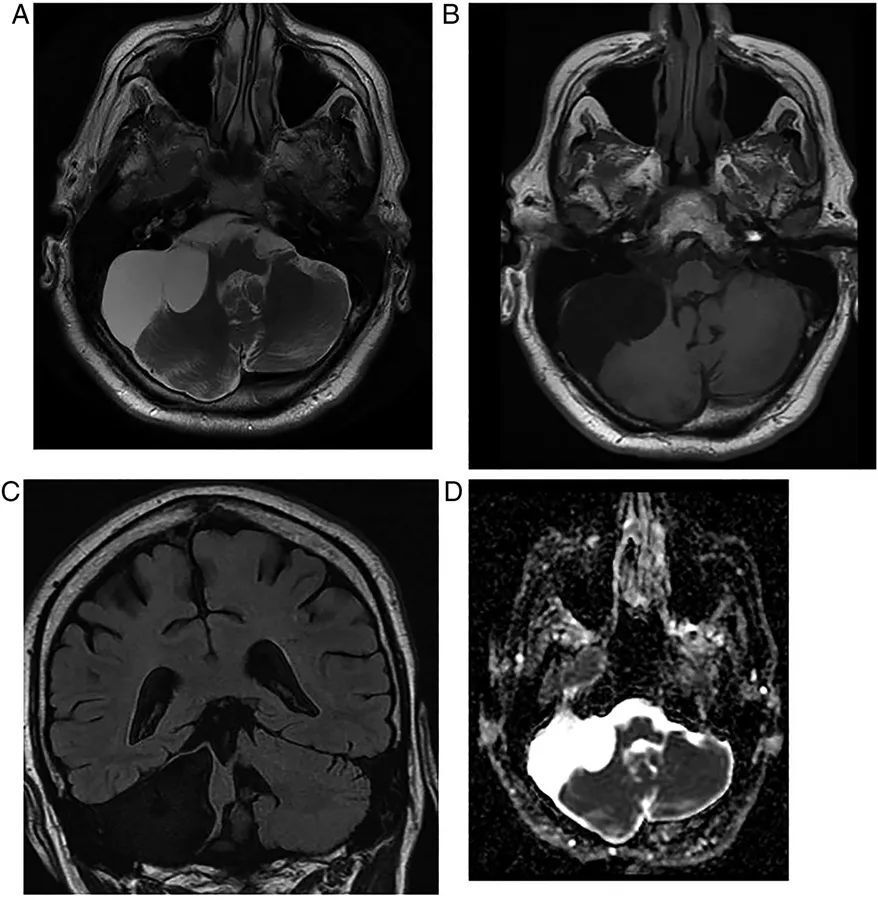

图14  脊索瘤。中线区可见一巨大不规则占位,斜坡和蝶窦被破坏,肿瘤延伸到右侧的脑池和桥小脑角区。脊索瘤在MRI上通常表现为T2高信号和T1上的局灶性高信号

图15  多发副神经节瘤。患者右侧有搏动性耳鸣,影像学可见右侧颈静脉球瘤以颈静脉为中心延伸到右侧桥小脑角,由血管流空信号和出血性变化组合而产生典型“胡椒盐”外观